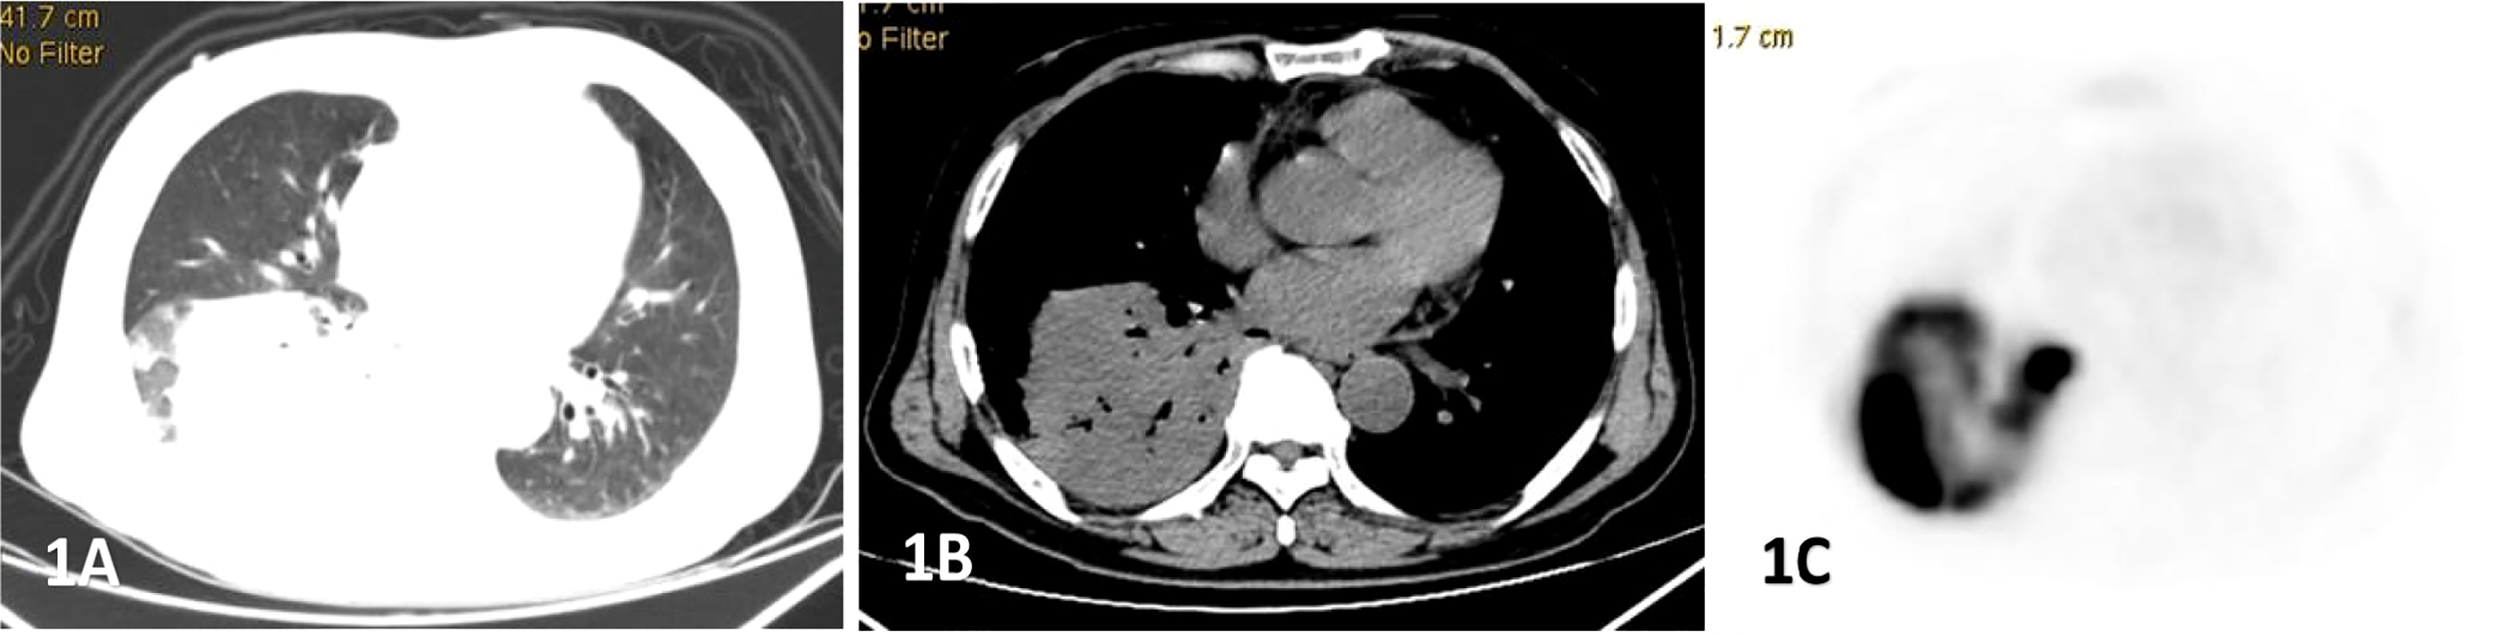

Figure 1

Male, 69 years old, fever, cough, dyspnea for 3 months. (A–C) showed lung, mediastinal CT scan and PET transection images respectively. Soft tissue mass shadow was observed in the lower lobe of the right lung, and aerated bronchial shadow was observed in the lesion, showing cross-lobe growth with a size of about 81×77mm.The FDG uptake of the lesion was significantly increased, with an SUVmax of 22.6. Percutaneous lung biopsy was conformed diffuse large b-cell lymphoma(DLBCL).